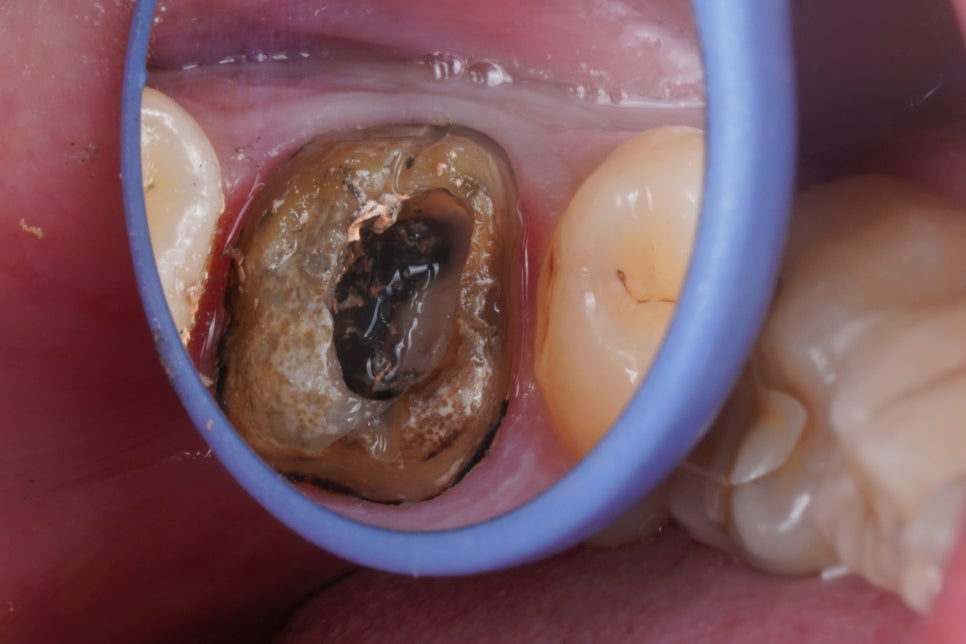

크라운을 벗겨내고

치아 내부를 관찰해봅니다.

굉장히 지저분하죠

크라운 내부, 치아의 외면은 물론

신경치료했던 치아 내부 역시

많이 오염되어있었습니다.